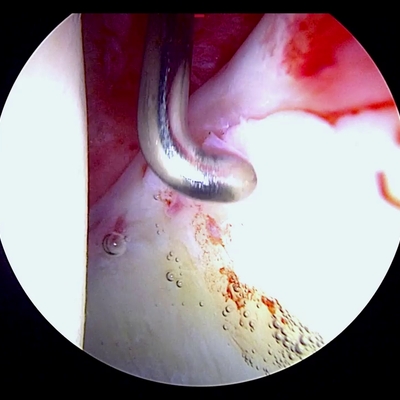

Click on an image below to view more info.